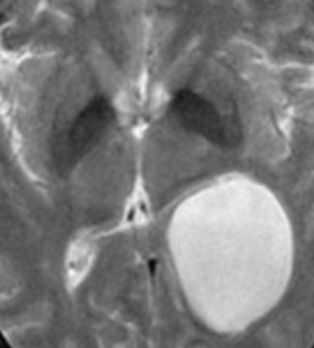

Киста кармана Ратке представляет собой редко встречающееся образование из остатков эмбриональной эктодермы (щель Ратке), расположенное между долями гипофиза. Выявляется в любом возрасте, но чаще в 50-60 лет. Клинические проявления связаны с масс-эффектом. При головного мозга выявляется небольшая (3-5 мм) киста с четким контуром, без отека вокруг, однородная по структуре. Сигнал зависит от содержимого. При серозном содержимом сигнал типично жидкостный, при мукоидном киста светлая на Т1-взвешенных МРТ. В редких случаях киста достигает больших размеров и даже выходит за пределы седла. Стенка кисты иногда усиливается при контрастировании.

МРТ головного мозга. Т2-взвешенная корональная МРТ. Киста кармана Ратке.

Киста кармана Ратке представляет собой редко встречающееся образование из остатков эмбриональной эктодермы (щель Ратке), расположенное между долями гипофиза. Выявляется в любом возрасте, но чаще в 50-60 лет. Клинические проявления связаны с масс-эффектом. При МРТ головного мозга выявляется небольшая (3-5мм) киста с четким контуром, без отека вокруг, однородная по структуре. Сигнал на МРТ головного мозга зависит от содержимого. При серозном содержимом сигнал типично жидкостный, при мукоидном киста светлая на Т1-взвешенных МРТ головного мозга. В 70-80% случаев внутри кисты выявляется неконирастирующийся узелок («пятно») - признак патогномоничный для кисты кармана Ратке. В редких случаях киста достигает больших размеров и даже выходит за пределы седла. Стенка кисты иногда усиливается при МРТ головного мозга с контрастированием. Дифференциальная диагностика при МРТ головного мозга должна проводиться с арахноидадьной и эпидермоидной кистами, тератомой, кистозной аденомой гипофиза и краниофарингиомой. Иногда при МРТ головного мозга киста кармана Ратке напоминает “пустое” турецкое седло. При маленьких размерах кисты ее на до дифференцировать на МРТ с микроаденомой гипофиза.

![Ratke cleft cyst]()

МРТ головного мозга. Т1-взвешенная сагиттальная МРТ. Киста кармана Ратке.